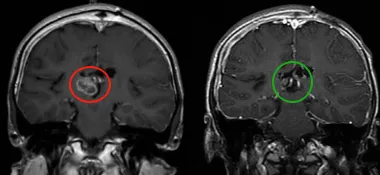

肿瘤伴钙化、瘤内出血,并伴有脑积水。磁共振成像(MRI)显示一个可能起源于透明隔的异质性强化肿瘤,填充在侧脑室和第三脑室的大部分区域。

第一次左额半球间经胼胝体切除术后,CT扫描显示脑室内和腔内出血。第二次经右顶叶经皮质入路成功实现次全切,术后显示为WHO 2级室管膜瘤。随后,为进一步控制残余肿瘤,鲁特卡教授为患儿制定了局部放疗方案。